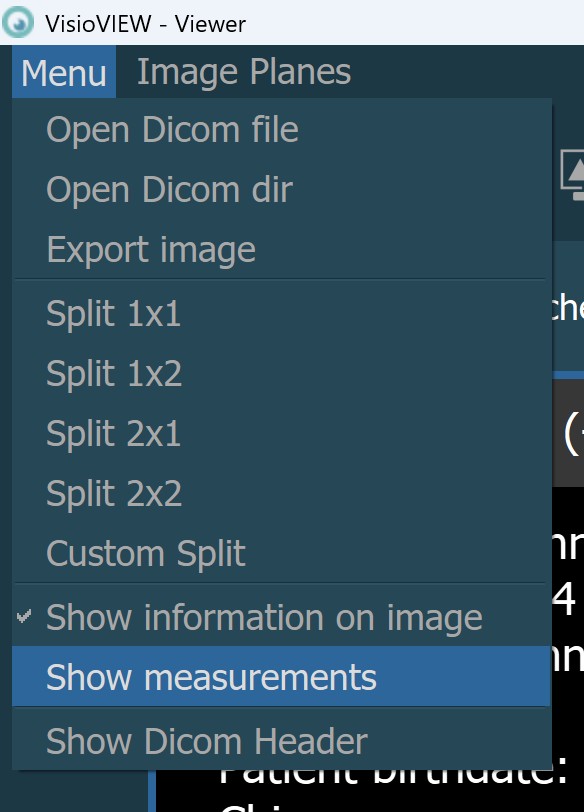

Additionally, the visibility of the measurements in the viewer area can be toggled by using the Menu -> Show measurements option from the Viewer menu.